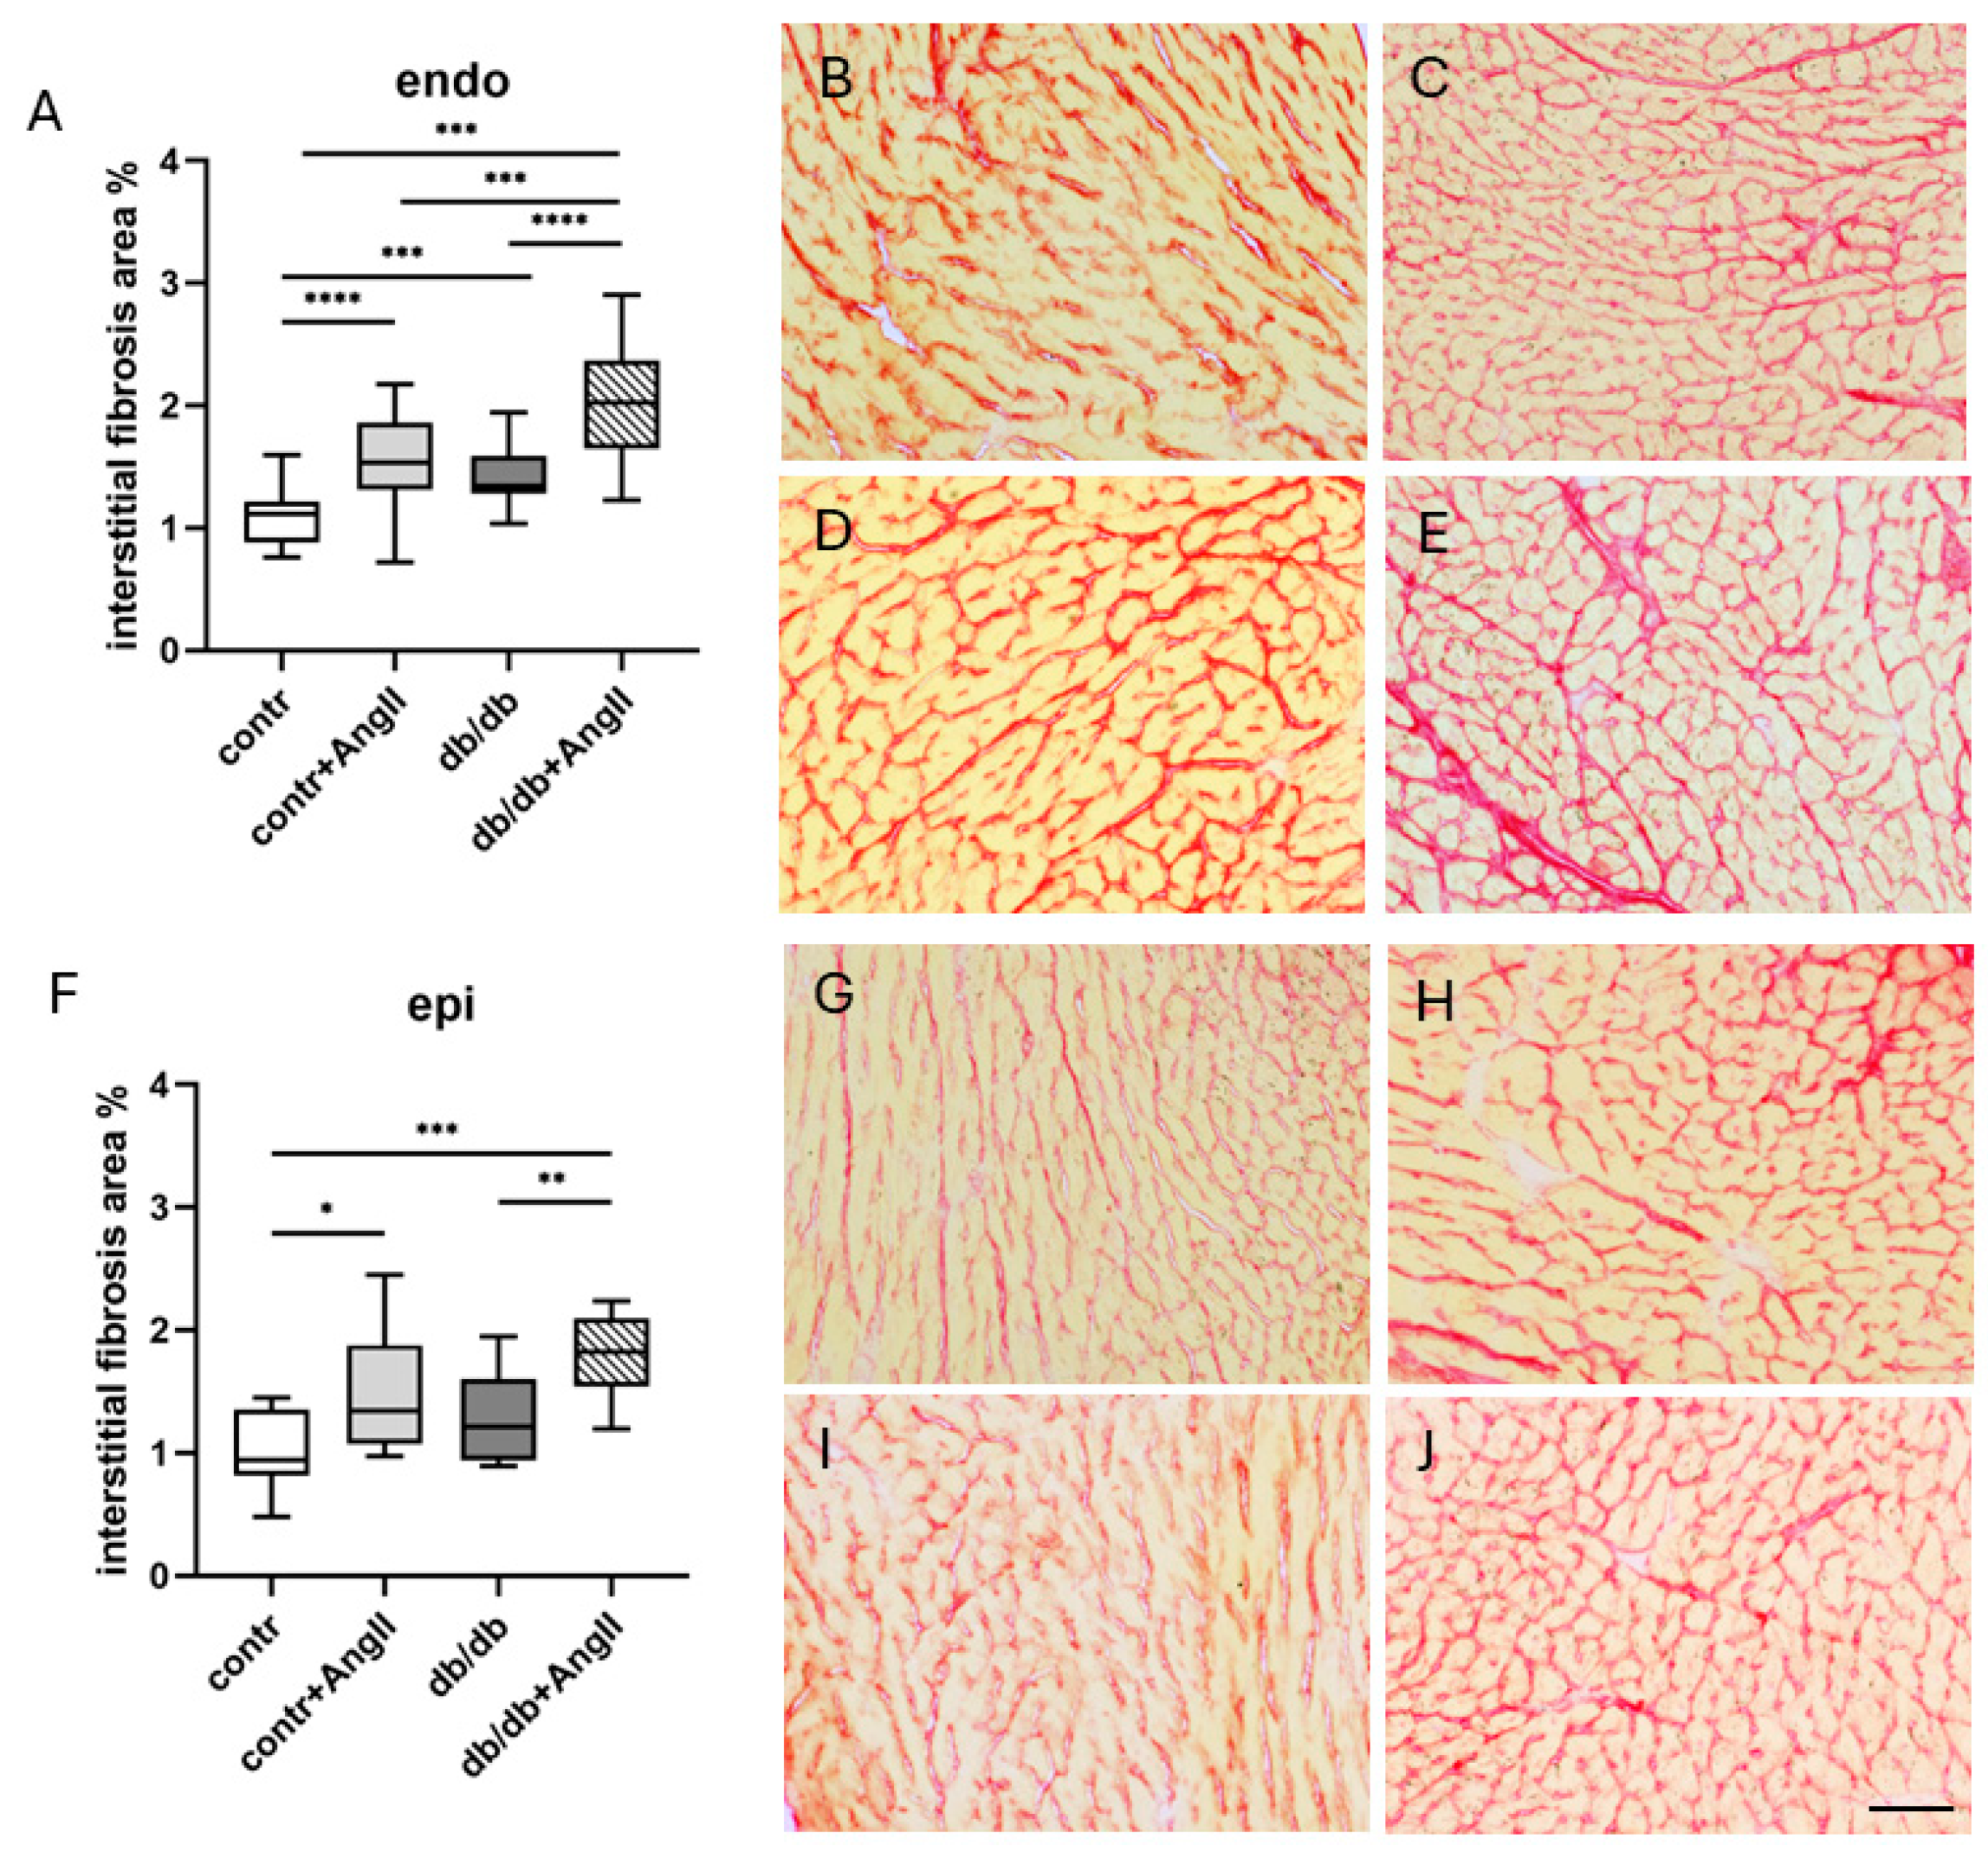

3.2. Heart Hypertrophy and Myocardial Remodeling

3.3. Cardiac LyV Density and Structural Remodeling